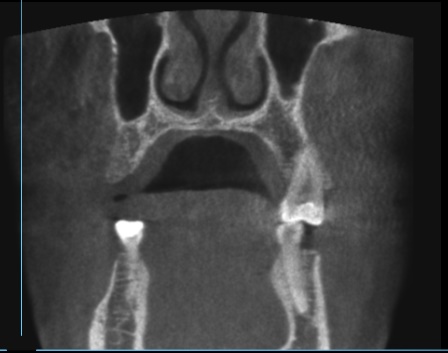

Пропила 2 курса антибиотиков. Хирург сказал, что все зубы в порядке, и отправил домой нервы лечить. Рентгенолог увидела повреждения и сказала не есть больной стороной и вообще не жевать. Это избавило меня от постоянной боли. Но стоит только дотронуться до семёрки, появляется неприятное очущение, как будто он висит на волоске. И в месте удалённой 5 зуд. Как будто кость сломана. Фото с 3д рентгена во время курса антибиотиков.

Прикрепленые фото

По этому снимку можно сказать, что немного повреждена передняя стенка, но это не является проблемой. К хирургу обратиться стоит, для того чтобы оценить процесс заживления.